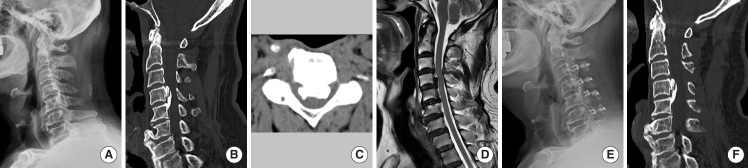

Methods: Patients with cervical myelopathy due to multilevel OPLL who underwent decompression surgery (anterior or posterior) from 2013 to 2022, with 2-year minimum follow-up, were enrolled. Radiological evaluations included K-line, COR, OPLL type/level, and cervical parameters (C2 slope [C2S], T1 slope [T1S], K-line tilt). Clinical outcomes included Japanese Orthopaedic Association (JOA) score and neck-pain visual analogue scale. Patients were categorized by K-line status (+/-) and COR (<50% or ≥50%).

Results: Among 575 patients, JOA recovery was significantly better in the K-line (+) and in low COR (<50%). In high COR (≥50%), K-line (-) was associated with poorer recovery. In low COR, outcomes were similar regardless of K-line. Anterior decompression with fusion (ADF) yielded the best outcomes. Laminoplasty (LP) was optimal for COR ≥50% and/or K-line (+), while laminectomy with fusion (LF) was better for COR ≥50% and K-line (-). In high COR, K-line was influenced by cervical alignment, C2S, and T1S, while in low COR, it was mainly affected by COR percentage.

Conclusion: Combining K-line and COR is essential for surgical planning in multilevel OPLL. When COR is high, K-line plays a significant role in predicting neurological recovery. ADF led to superior recovery, whereas for patients with K-line (-) and high COR, LF offered better results than LP. Cervical parameters at high COR influence the K-line more.